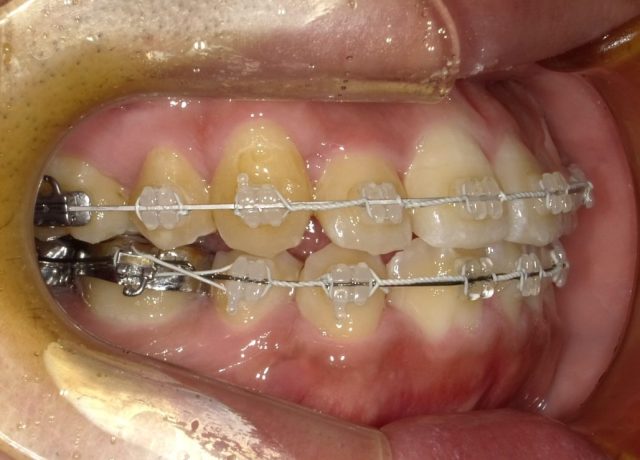

【右側面観】

2023年1月

| 治療方法・治療内容 | 4本抜歯・フルブラケット・ストレートワイヤーテクニック |